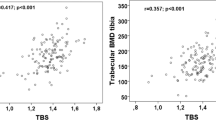

Baseline scan data are presented in Table 2. One woman did not complete DXA scans. Furthermore, one LS scan was excluded, as unreliable, due to degenerative changes (osteophytes) in the spine. There were no differences between groups for DXA aBMD at baseline. For HR-pQCT scans, seven radius and two tibia scans were removed due to motion scores exceeding our criteria. In addition, two radius and three tibia scans were removed from analysis due to scan abnormality (large holes in the trabecular bone region) or artifact. There was no between-group difference in the percent overlap of baseline and follow-up scan regions (radius 90% overlap; tibia 94% overlap). At the radius, baseline results show post-menopausal women had lower BMD (Tt.BMD and Ct.BMD), Tb.N, Ct.Th, Ct.Ar and failure load than peri-menopausal women, with higher Ct.Po. At the tibia, post-menopausal women had lower BMD (Tt.BMD and Ct.BMD) and higher Ct.Po than peri-menopausal women.

At the tibia, there were significant differences in the rate of change between groups for Ct.Po and Tt.Ar. Peri-menopausal women had a + 9% per year increase in Ct.Po compared with +6% per year for post-menopausal women. In addition, post-menopausal women had an increase in Tt.Ar of +0.13% per year compared with +0.06% per year for peri-menopausal women. The rate of change between groups was not significantly different for any other microarchitecture, density, geometry, or strength measures at all skeletal sites measured. Other than menopause status, age, the number of years past final menstrual period, and osteoporotic medication did not contribute to rate of change differences between groups.

There were significant differences in microarchitectural parameters at the tibia that may be indicative of accelerated remodeling during the menopause transition. Using HR-pQCT, we found an increased rate of cortical porosity in peri- compared with post-menopausal women, whereas we failed to observe differences in rate of change of trabecular microarchitecture within groups at the tibia. These data suggest that within the age range of our participants, cortical bone changes occur at a higher rate than trabecular bone changes. Similar results have previously been observed following menopause [28, 29]. The increased rate of change in Ct.Po observed in peri-menopausal women is consistent with data showing increased bone remodeling due to estrogen deficiency [30], and is thought to be associated with cortical bone loss [31]. The fact that the trabecular area increased and the cortical area decreased during the transition, coupled with the increased cortical porosity, suggests that endocortical remodeling likely underpins the cortical bone loss.